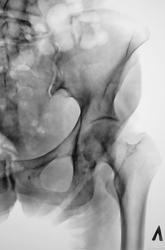

Газовая атака какая-то. Костная структура головок неоднородная, болье слева, а "преклонный" возраст может быть связан с остеопорозом и кистовидными просветлениями. А по поводу чего ее обследуют-коксартроз, новообразования и тд?

Вот мы и нашли: газ и содержимое толстой кишки.

Единственная зацепка. Остальное - по возрасту и кишкам. Ну и сноска на укладочку допустима у старушек.

Я бы не стал все списывать на газ. Многие просветления в костях подозрительны на остеолитические метастазы.

Пациентке животик бандажиком поприжать и сделать косые снимочки, снимая/подтверждая подозрения всех участников художественного марафона.